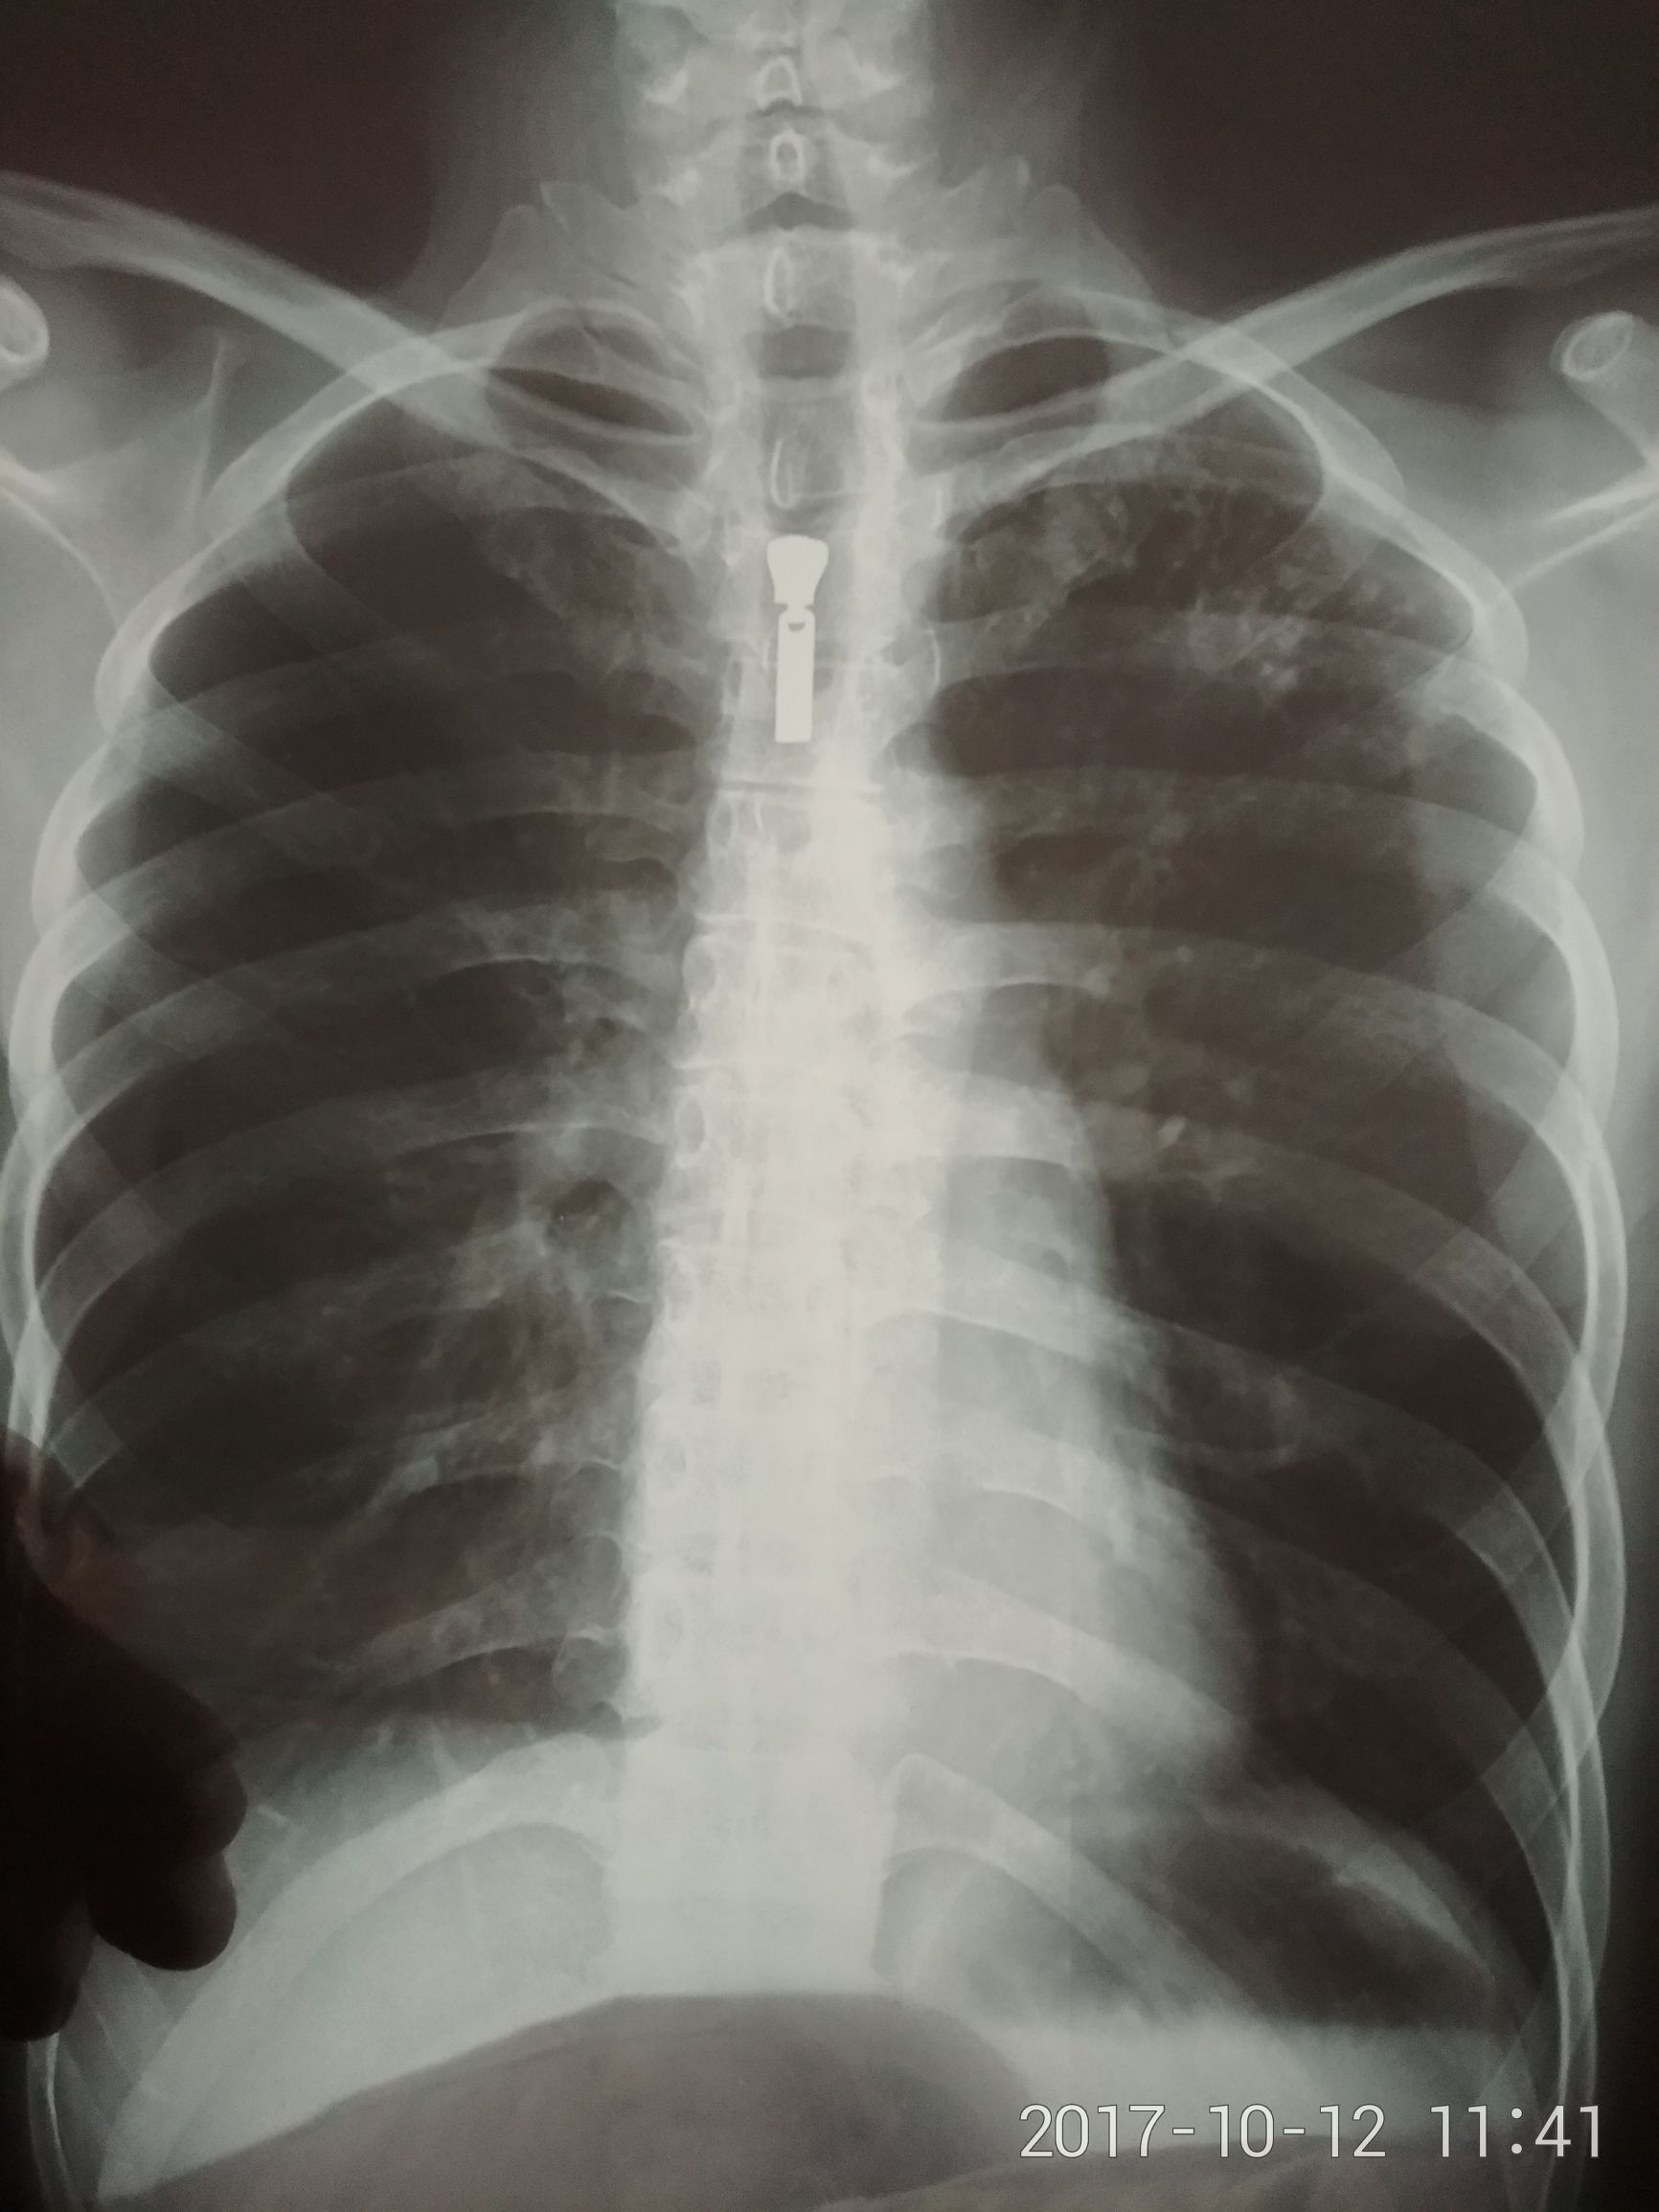

挂了号,大夫稍微一问,咯血了?去拍胸片吧,拍完等了一会,放射科大夫说有一块阴影,看起来可能是炎症或者结核,之前没了解过结核这种病,以为这肯定是老年人得的,自以为可能是个炎症吧,拿去给大夫一看,说很可能是肺结核,让我明天去市里传染病医院继续诊断,给我写了张介绍信一样的东西,然后回到家,马上躺床上不敢乱动,8点多就准备睡觉,怕咯血,平时夜里一两点前基本上没睡过觉,就这晚上还是有一次吧,咯了一点点血,第二天早上醒来也有一点点,下面放上胸片。

抗核日记:一个肺结核患者的治疗过程㈠ ​左边是右肺,右边是左肺,可以看出左肺上面有一块白色的阴影,这个叫病灶,就是说肺上有问题了,有的严重的空洞型肺结核胸片上就能看出明显空洞,我这个算轻的了,胸片只能看到这种地步,想再看清楚点就得做ct了。